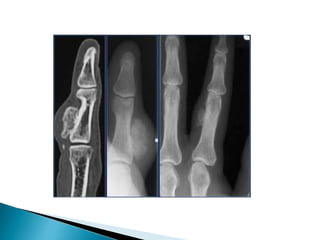

Here on a radiograph thetypical calcification s in the chondroid matrix of an enchondro ma Notice how easily MRI depicts these

 Most commonlyencountered bone tumor in the small bones of the hand and foot.  .Enchondroma is a fairly common benign cartilaginaous lesion which may present as an entirely lytic lesion without any calcification, as a dense calcified lesion or as a mixed leson with osteolysis and calcifications.  Enchondromas aswell as low-grade chondrosarcomas are frequently encountered as coincidental findings in patients who have a MRI or bone scan for other reasons.